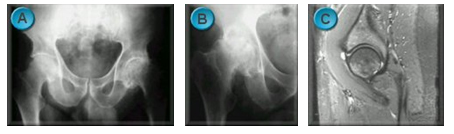

When your hip is arthritic and painful the options for treatment are limited (image A). Painkillers and anti-inflammatories can help temporarily but often the side effects are unpleasant. Sometimes an injection of local anaesthetic and steroid is used to relieve severe symptoms for a few months. With time the hip may stiffen and become less painful, but it may collapse causing the leg to shorten, making surgery more complex (image B).

Certain conditions may be amenable to keyhole surgery, usually after an MRI scan has been performed (image C). If the pain is getting worse and is affecting your mobility, then you might wish to consider having a hip replacement or resurfacing.